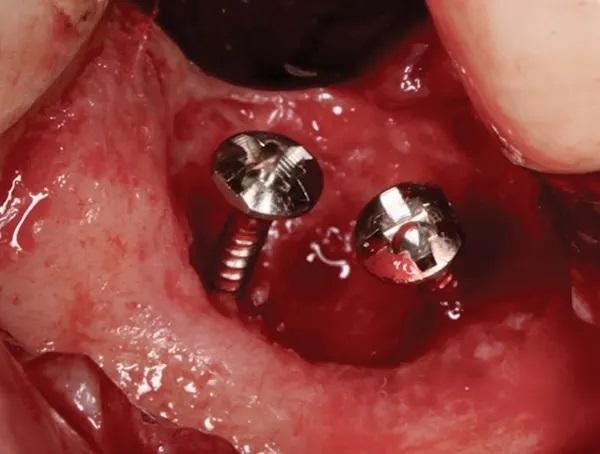

Дефект был тщательно дегранулирован и промыт физиологическим раствором. Затем была выполнена декортикация с использованием алмазного круглого бора № 6 и высокоскоростного хирургического наконечника. Два фиксирующих винта (головка винта диаметром 3 мм x хвостовик диаметром 1,5 мм x общая длина 7 мм) были помещены в дефект, чтобы закрепить аллотрансплантат и коллагеновую мембрану и добиться желаемого вертикального и горизонтального увеличения объема альвеолярного отростка (фото 7).

Фото 7. Показан кратерообразный комбинированный дефект от одной до двух стенок с двумя крепежными винтами, стратегически расположенными для натяжения мембраны и достижения идеальной высоты и ширины.